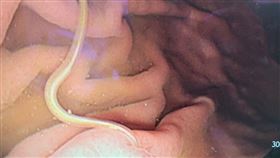

27歲孕婦吃水果腹痛 住院吐2條生猛蛔蟲

除了生魚片,吃水果也會排出寄生蟲?泰國一名27歲孕婦...

病人吃1物竟寄生蟲埋胃!醫:一輩子陰影

生魚片這項料理深受許多民眾喜愛,但最怕因為不新鮮吃進...